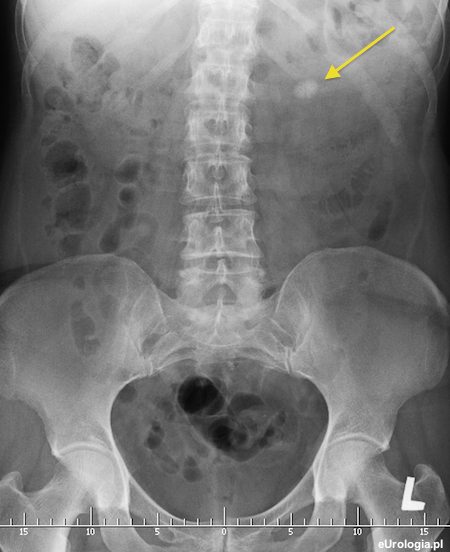

Fot. Zdjęcie przeglądowe jamy brzusznej z cieniem wapiennym będącym złogiem około 2 cm w grupie dolnej kielichów lewej nerki.

Bezobjawowa kamica dolnego kielicha przy prawidłowym badaniu ogólnym moczu nie jest wskazaniem do interwencji urologicznej. Warto zastanowić się czy nie kontrolować okresowo złogu w USG i ewentualnie przypoadku pojawienia się dolegliwości lub narastania złogu zdecydować się na leczenie operacyjne.

Najmniej inwazyjnym sposobem leczenia kamicy dolnego kielicha jest PCNL - przezskórna nefrolitotrypsja. Ze względu na wymiar kamienia i jego lokalizację w dolnym kielichu ESWL może być mało skuteczne. Pacjenci, u których są wskazania do leczenia operacyjnego a PCNL nie przynosi efektu mogą być operowani klasyczni - operacja otwarta.